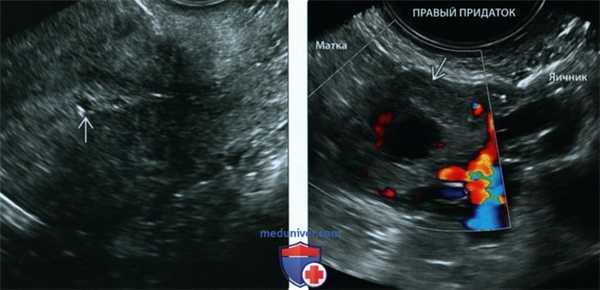

Внематочная беременность маточных труб может также рассматриваться как эхогенное кольцо в придатках, окружающее неразрывную внематочную беременность, которая известна как знак трубного кольца (Рис. 4А). Это второй по частоте признак внематочной беременности и имеет 95% положительную прогностическую ценность. Цветовой допплер часто показывает кольцо периферической сосудистой системы (Рис. 4В).

Рисунок 4: Трубно-кольцевой знак.

У этой 20-летней женщины с положительным тестом на беременность, поступающей в отделение неотложной помощи с болями в области таза и вагинальными выделениями, имеется придаточная масса с эхогенным кольцом (стрелка). B. Цветное доплеровское изображение правого придатка показывает увеличенную васкуляризацию в эхогенном кольце. У пациентки была диагностирована внематочная беременность на основании клинической и сонографической оценки, и она успешно лечилась метотрексатом.